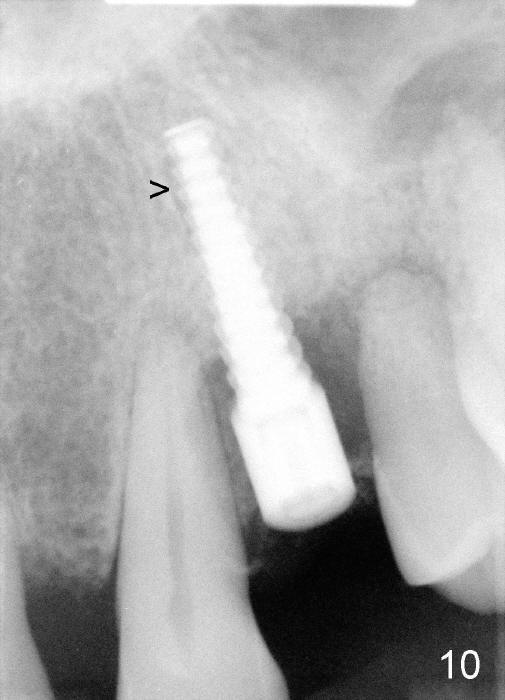

Dear Drs. Dunson and Borgner: Thank you for support. Fig.5 and 6 taken immediately prior to surgery show that the healing socket is elliptical (arrowhead). After D1 and D2 channel formers, D2 thin socket former is tapped in (Fig.7). The osteotomy needs to be redirected as shown by the black line. D2 implant is being inserted with Synthograft applied to the 1st two threads (Fig.8) and is in place (Fig.9,10). But the implant is not as stable as expected. There is a gap mesial to the implant (Fig.10 arrowhead), which is most likely created by re-directing the osteotomy with channel and socket formers.

Crestal bone grows 2 months (Fig.11), 3 months (Fig.12), 1 year (Fig.13) and 2 years 3 months (Fig.14) postop. When the periodontally-affected tooth is removed and bone graft is placed around the most coronal thread of the implant, bone will regrow as time passes by.